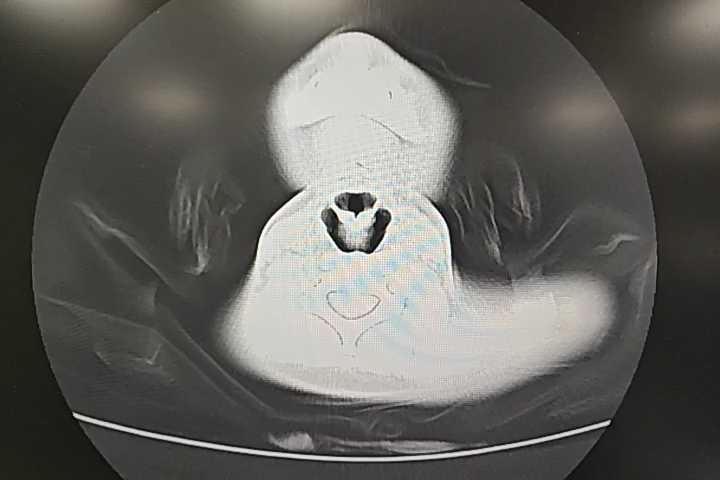

入院后予阿奇霉素抗感染、奥美拉唑护胃等治疗2天,患儿无呕血,有低热。支原体DNA结果回报(+)。入院第三天,患儿再次出现高热,39.5℃,考虑混合流感感染可能,予口服奥司他韦治疗。因听诊肺部无明显啰音,暂不建议进一步检查。不过家属要求胸部CT检查,结果如下

提示右肺上叶肺炎伴阶段性实变、不张。加用激素抗炎治疗,体温较前好转。肺炎支原体感染的患儿,对于病程短,入院抗感染治疗后,体温反复的,除了考虑院感,还需要考虑抗感染效果不佳,同时需考虑胸部CT检查。今年肺炎支原体挺多的,各位老师有什么经验,分享一下!!!